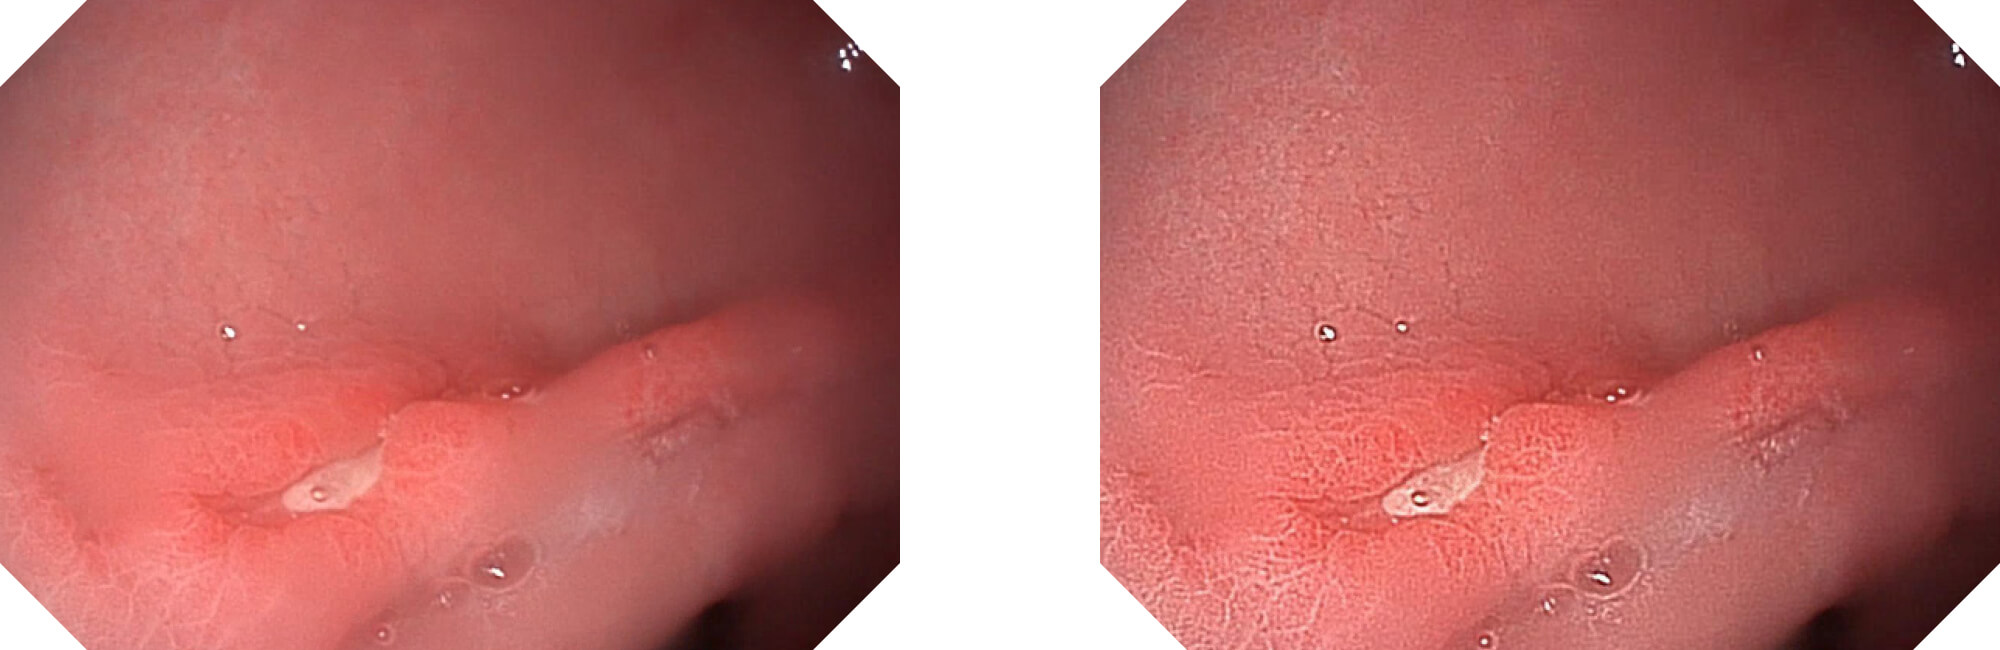

高清数字信号结合构造强调和色彩增强,多重图像处理技术能让每一个图像都清晰可见。

构造强调

色彩增强

电子放大